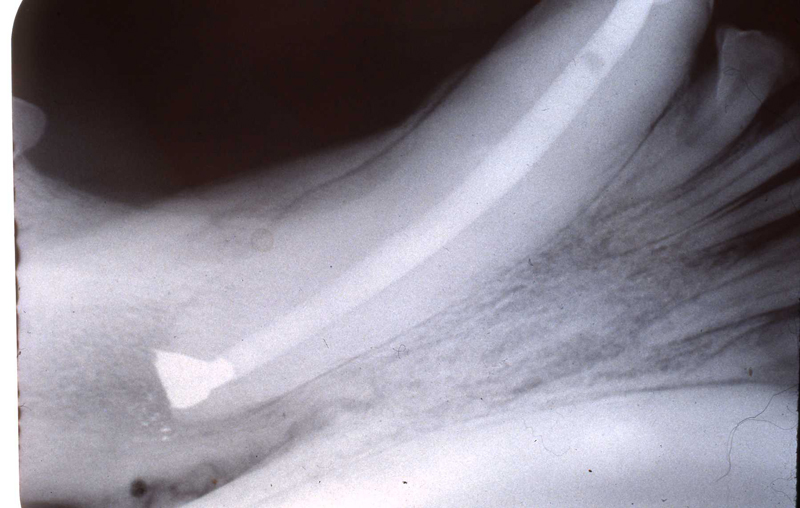

A horizontal incision was made rostral to the medial canthus of the eye, dissecting to bone. The patients' eyes were draped for protection. A 558 surgical bur in a water cooled high speed dental handpiece was used to cut through the bone and expose the canine apex and lesion.

The periapical lesion was debrided with small bone currettes. The exposed root apex was sectioned. Endodontic files were used to debride the entire root canal from the coronal end. Sodium hypochlorite and RC Prep (Root Canal Preparation©, Premier Dental Products, Co., 3600 Horizon Drive, King of Prussia, PA 19406-0974) was used to irrigate the canal during filing When the canal was prepared, irrigated, and dried, a PC pressure syringe (Pulpdent Corporation Pressure Syringe©, Pulpdent Corporation, 80 Oakland Street, Watertown, MA 02471, USA), was used to deposit the zinc oxide/eugenol paste until it extruded apically. Gutta percha points were fitted, placed and laterally condensed. A retentive preparation was made at the apical and coronal ends, and silver amalgam was used to seal the preparations. The surgical site was irrigated with sterile saline and closed with dissolving sutures.

lnteroperative and postoperative radiographs were obtained to verify endodontic working length and extent of endodontic fill.